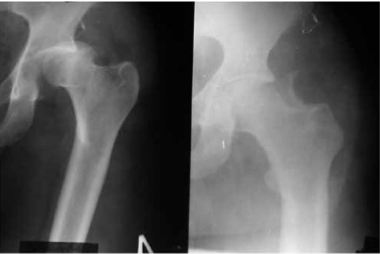

Для ранней активизации больного операция заканчивается установкой аппарата внешней фиксации. Аппарат позволяет гарантированно стабилизировать тазобедренный сустав с заданной или регулируемой разгрузкой, что создает условия не только для срастания перелома, но и для расправления или восполнения участков импрессии или компрессии с восстановлением структуры субхондрального слоя (рис. 2, 3).

Обзорная рентгенограмма таза. Состояние после открытой репозиции и фиксации верхнего отдела заднего края вертлужной впадины винтом. Стабилизация и разгрузка тазобедренного сустава в аппарате внешней фиксации

Рентгенография тазобедренного сустава в двух проекциях (прямая и аксиальная). Срок после оперативного лечения — 6 лет